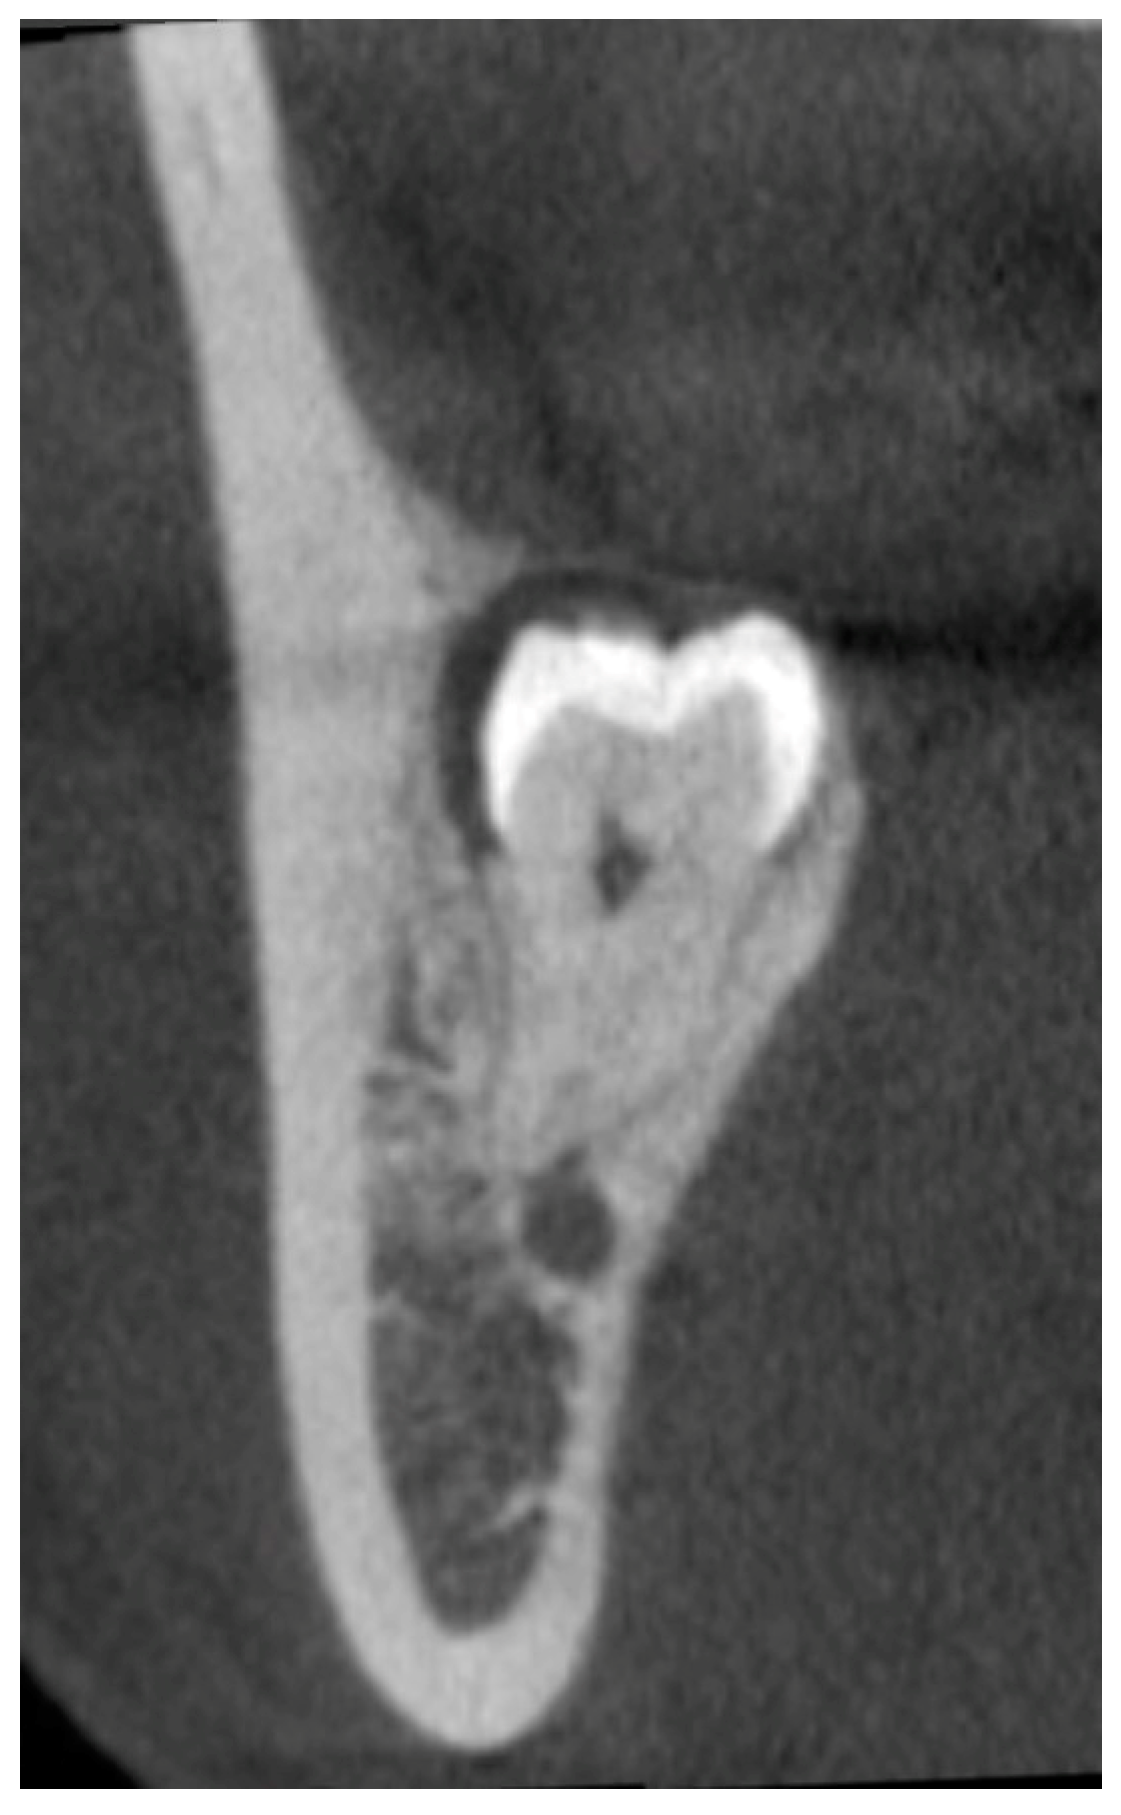

In third molar surgery, CBCT offers a thorough understanding of the 3D relation between the third molar and the IAC [33]. The bone and tooth structure in cross-sectional images can be clearly displayed in CBCT, as well as their spatial relationship. Moreover, the bucco-lingual position of the overlapping hard tissue structures can be demonstrated, as well as the type of third molar impaction and the specific number and morphology of the root(s). Since IAN injury is directly related to the contact of the root and the IAC, visual confirmation by a coronal CBCT image to demonstrate the true contact between the two structures is the solid proof of their relationship (Figure 2). Tantanapornkul et al. noted that CBCT carried a sensitivity and specificity of 93% and 77%, respectively, to predict IAN exposure, which was significantly higher than OPG [34]. Hasani et al. performed a prospective study to compare CBCT and OPG in predicting IAN exposure after third molar surgery and found that CBCT was accurate in 93.3% of the cases, which was much higher than the 67.7% by OPG [35]. Reia et al. performed a systematic review and meta-analysis and confirmed that CBCT was superior in predicting IAN exposure [36].

Figure 2.

Representative CBCT image showing the loss of the upper cortex of the inferior alveolar canal.